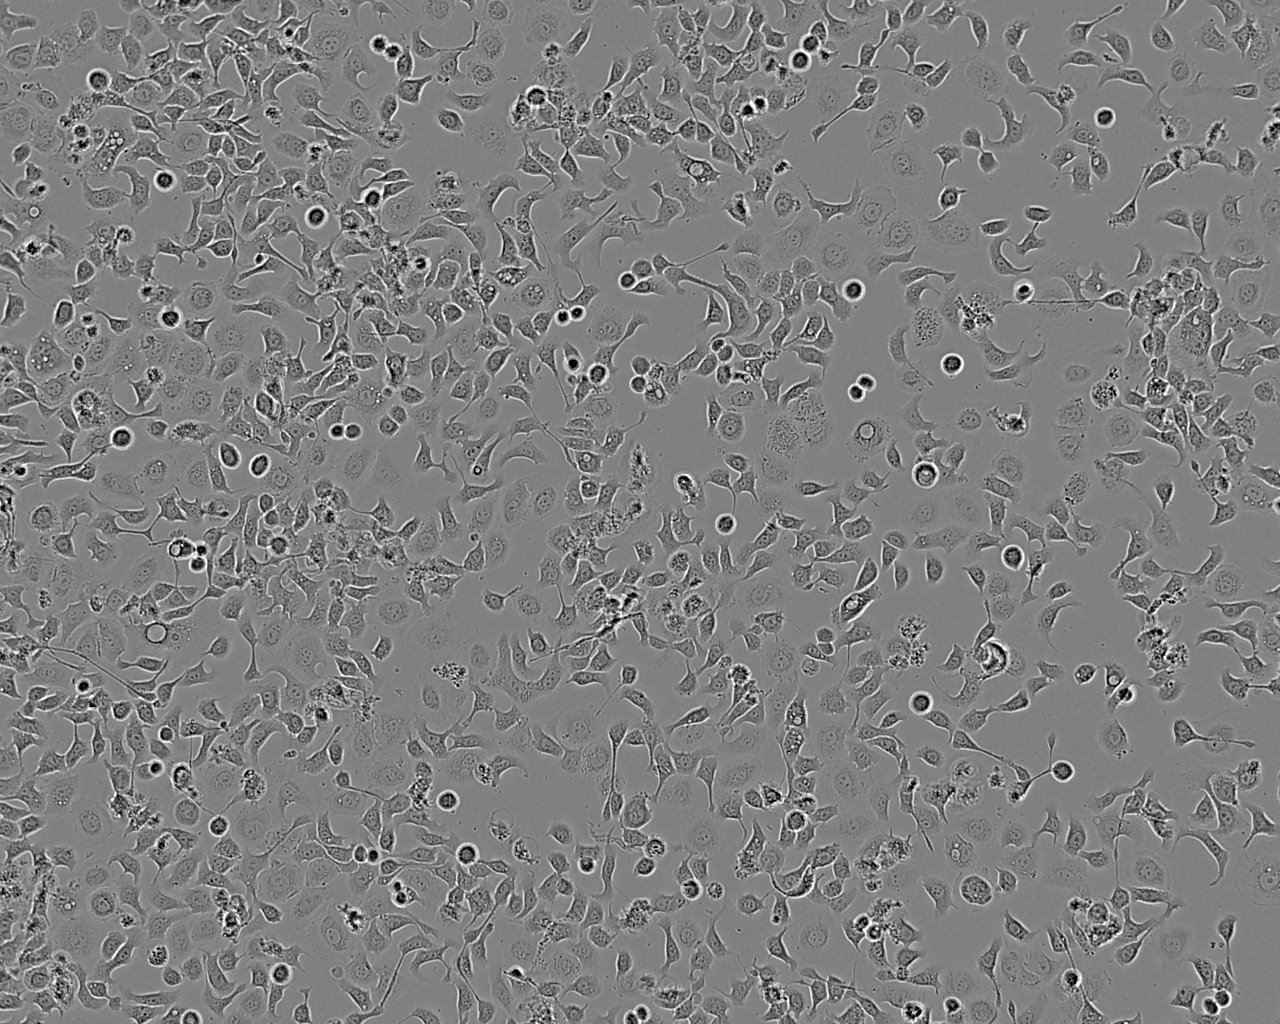

Split sub-confluent cultures (70-80%) up to 1:5 i.e. seeding at 1-3 x 10,000 cells/cm² using 0.05% trypsin or trypsin/EDTA; 5% CO₂; 37°C.